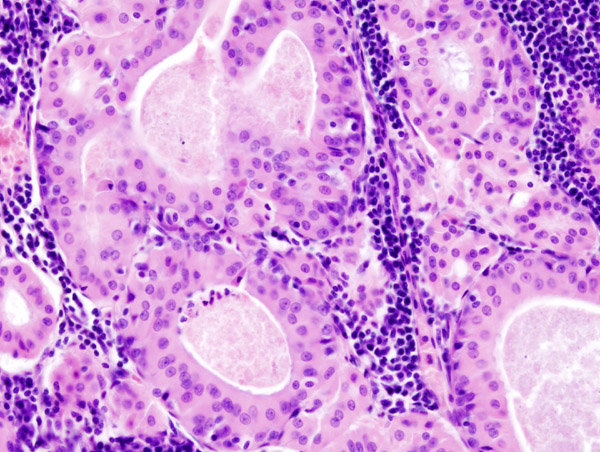

Warthin Tumor

Warthin tumor is a benign cystic tumor with a stroma that resembles a lymph node and many lymphocytes.

Warthin tumor is also known as papillary cystadenoma lymphomatosum.

Warthin tumor is the second most common salivary gland tumor.

Warthin tumor occurs almost invariably in the parotid.